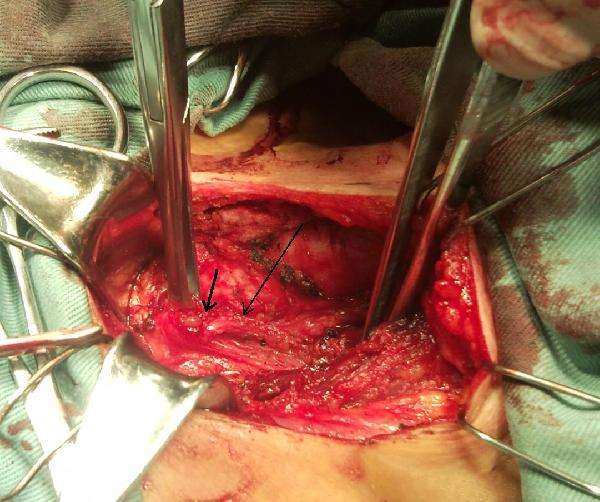

雙側葉甲狀腺癌手術解說

晚期甲狀腺癌手術

手術治療甲狀腺癌

甲狀腺癌治療手術